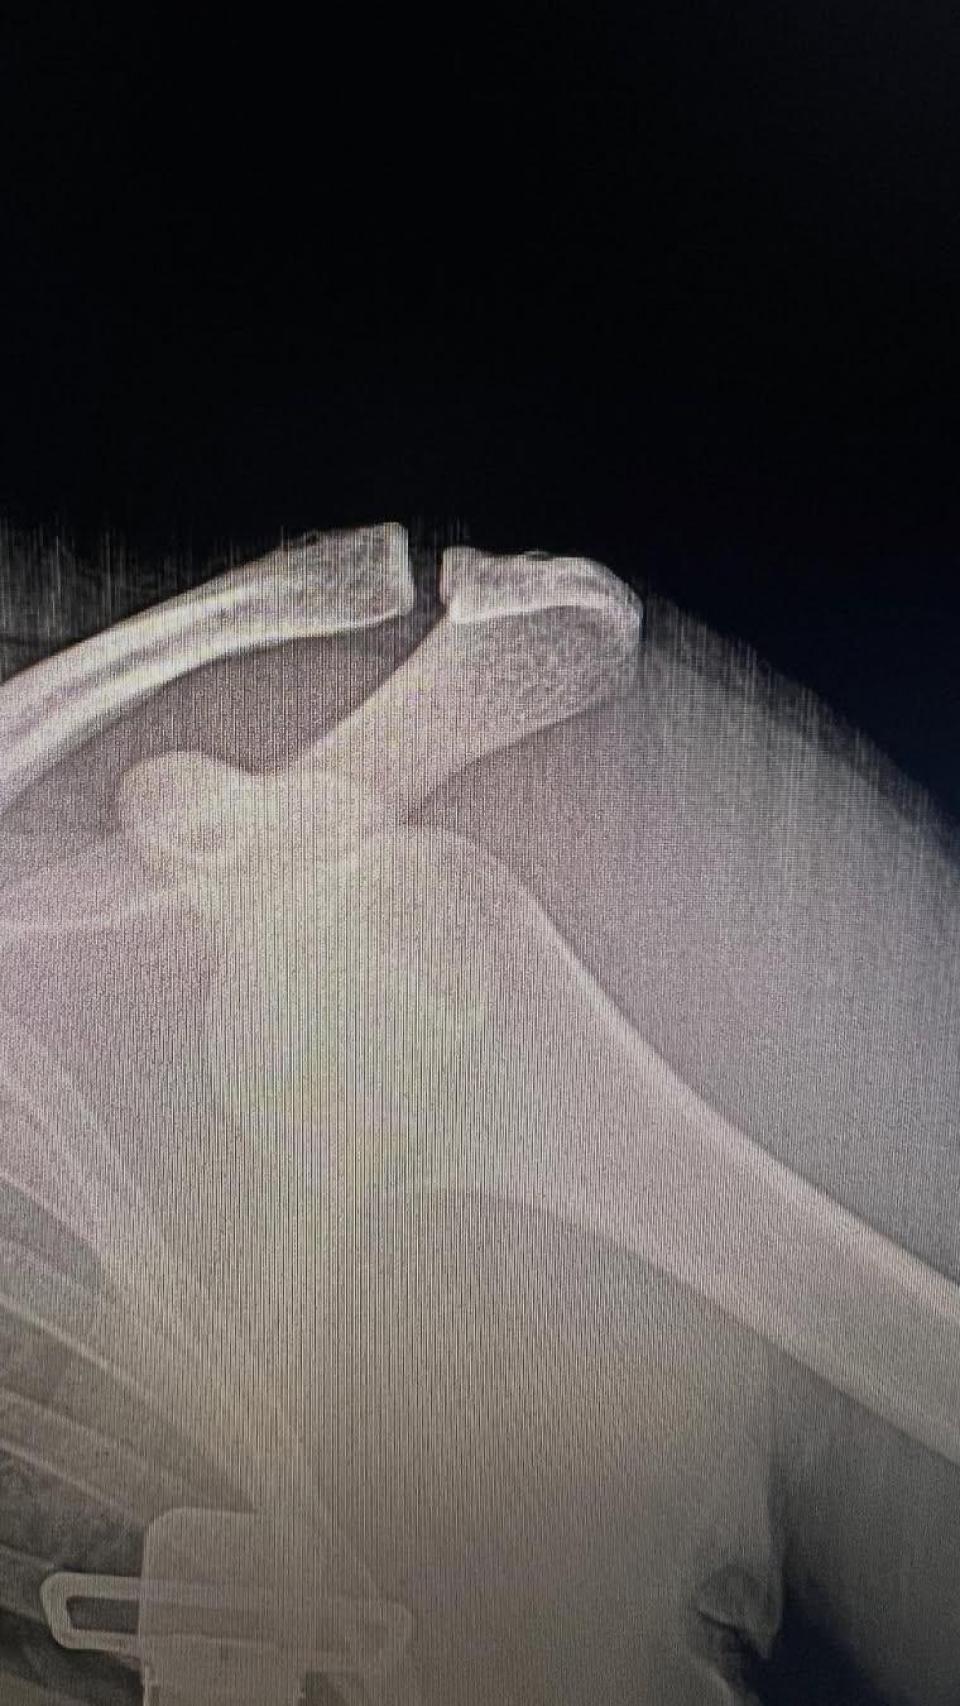

Incluso ha publicado una radiografía de su lesión, en la que se observa con todo lujo de detalles cómo los huesos del brazo han salido de su posición normal en la articulación del hombro.

El político ha compartido en su perfil de Instagram una radiografía de su hombro, que ya está recuperado.

El político ha compartido en su perfil de Instagram una radiografía de su hombro, que ya está "recuperado". Instagram